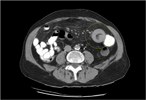

Conservative management of a traumatic common iliac venous pseudoaneurysm: a case report

Walker Lyons and others

Journal of Surgical Case Reports, Volume 2017, Issue 5, May 2017, rjx085, https://doi.org/10.1093/jscr/rjx085